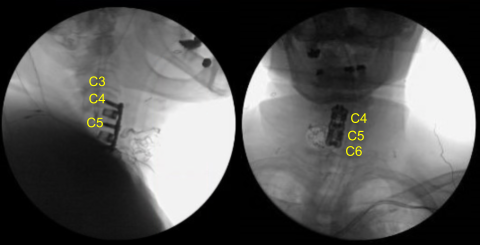

Blunt dissection and Cloward handheld retractors were used to approach the anterior cervical spine. Kittners were used to sweep the prevertebral fascia. A spinal needle was placed into the C5-C6 interspace. The C-arm unit was draped sterilely, brought into the field and used to confirm the level.

Bovie monopolar was used to expose the anterior cervical spine from C4 to C6 undermining bilateral longus colli muscles. TrimLine self-retaining retractor system was placed. Caspar pins 12 mm were placed into the C4, C5 and C6 anterior vertebral bodies. Gentle retraction was applied first across C5-6.

AP and lateral fluoroscopy showed correct positioning. Motor evoked potentials showed slight decrease in amplitude in the right C5-6. The instrumentation was then removed. The instrumentation space was cleaned out and irrigated flush.

Fluoroscopy showed correct sizing and positioning, so it was secured with six 14 mm titanium screws decorticating with a handheld 12 mm electric drill. AP and lateral fluoroscopy showed good positioning. All the screws were final tightened using an integrated device in the plate.